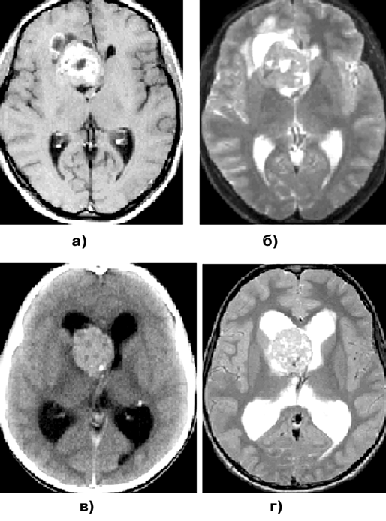

Для доброкачественных диффузных астроцитом при КТ наиболее характерна зона понижения плотности, не имеющая четких границ с окружающим мозговым веществом (рис. 1а, г). Внутривенное введение контрастного вещества обычно не приводит к повышению рентгеновской плотности очага. Разрешающая способность КТ недостаточна для идентификации границ опухоли, особенно изоплотностной по отношению к мозговому веществу.

МРТ — более точный метод визуализации астроцитом. Доброкачественные астроцитомы представляются изо— или гипоинтенсивными на Т1-взвешенных изображениях (рис. 1б, д). В режиме Т2, наиболее информативном при данной патологии, эти опухоли могут выглядеть как сравнительно хорошо отграниченная зона гомогенно повышенного сигнала (рис. 1в, е). “Масс-эффект” выражен, как правило, незначительно, контраст накапливается редко. Так как эти опухоли обычно диагностируются только на стадии выраженных клинических проявлений, для них типично поражение одновременно нескольких долей мозга. Перифокальный отек не характерен.

Рисунок 1. Астроцитомы:

а — астроцитома левой заднелобной области (КТ с контрастным усилением); б — астроцитома левой заднелобной области (МРТ, Т1-взвешенные изображения); в — астроцитома левой заднелобной области (МРТ, Т2-взвешенные изображения); г — фибриллярная астроцитома правой лобно-височной области (КТ с контрастным усилением); д — фибриллярная астроцитома правой лобно-височной области (МРТ, Т1-взвешенные изображения); е — фибриллярная астроцитома правой лобно-височной области (МРТ, Т2-взвешенные изображения)